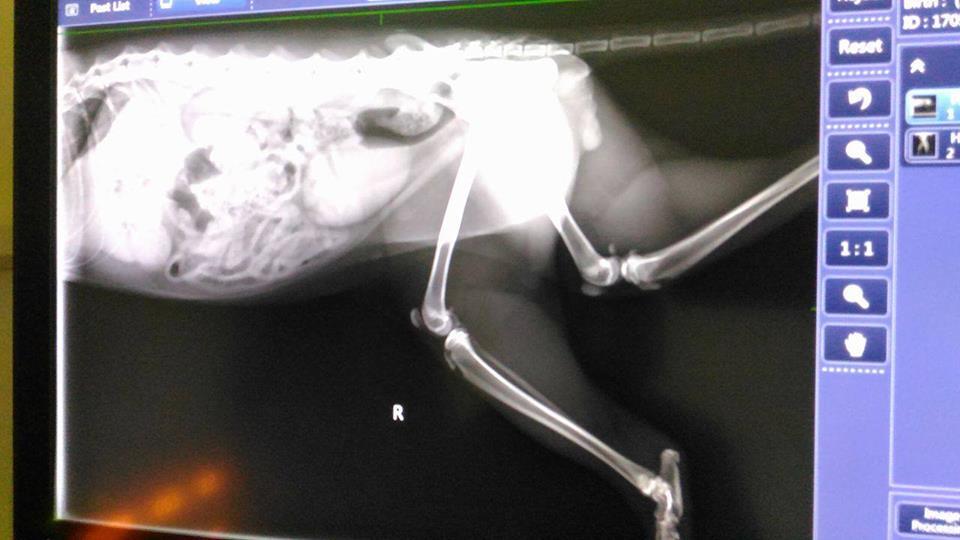

腳的骨頭沒有什麼問題,下週回診看傷口狀況如何,就可原放~

5/23 澄諾回診 車禍貓(小智) 3.22KG

【回診狀況】

小智的傷口,復原的還不錯,醫生把痂給剝掉,只剩下最底層的傷口還沒好,要注意小智會不會去舔傷口,再吃一週抗生素,下禮拜只要拍照回傳傷口狀況就好。

【餵藥】

抗生素,早一次,一次一顆

【注意事項】

觀察有無舔傷口

【下次回診】

無,只需拍照傷口狀況回傳